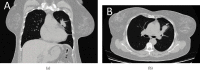

Background: Colorectal cancer metastasis to the thyroid is extremely rare and happens in the late course of the disease. Case Description. Here is the report of a 55-year-old female patient who came to us with the chief complaint of cough, diagnosed with colon metastasize to the lung. Surgical resection of the mass was performed. However, a thyroid mass was found incidentally in her postoperative follow-up. Fine needle aspiration of thyroid mass showed papillary thyroid carcinoma. But, after thyroidectomy, the origin of the mass was reported to be adenocarcinoma metastasis from colon cancer.